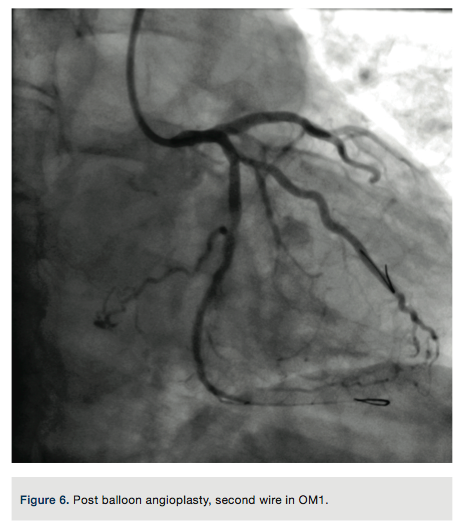

A Pilot 200 wire (Abbott Vascular) was loaded in a CrossBoss catheter (Boston Scientific) and advanced into the circumflex artery. The CrossBoss was slowly advanced, using the Pilot wire to redirect the device to remain as close to the lumen as possible. Once past the total obstruction, the Pilot 200 wire was used to re-enter the distal circumflex (Figures 3-4). A balloon dilation with a 1.5 mm x 20 mm long balloon was performed at 12 atmospheres (atm) followed by a 2.5 mm x 20mm balloon at 12 atm. A Runthrough wire (Terumo) was placed in the first marginal and stenting of the circumflex was performed using a 2.5 mm x 38 mm Promus Premier stent (Boston Scientific) overlapped with a 3.0 mm x 24 mm Promus Premier stent. High-pressure inflation in the entire stented segment was performed using a 3.0 mm balloon. The segment proximal to the first obtuse marginal was dilated to high pressure using a 3.25 mm balloon (Figures 5-7). A good angiographic result was seen (Figure 8).